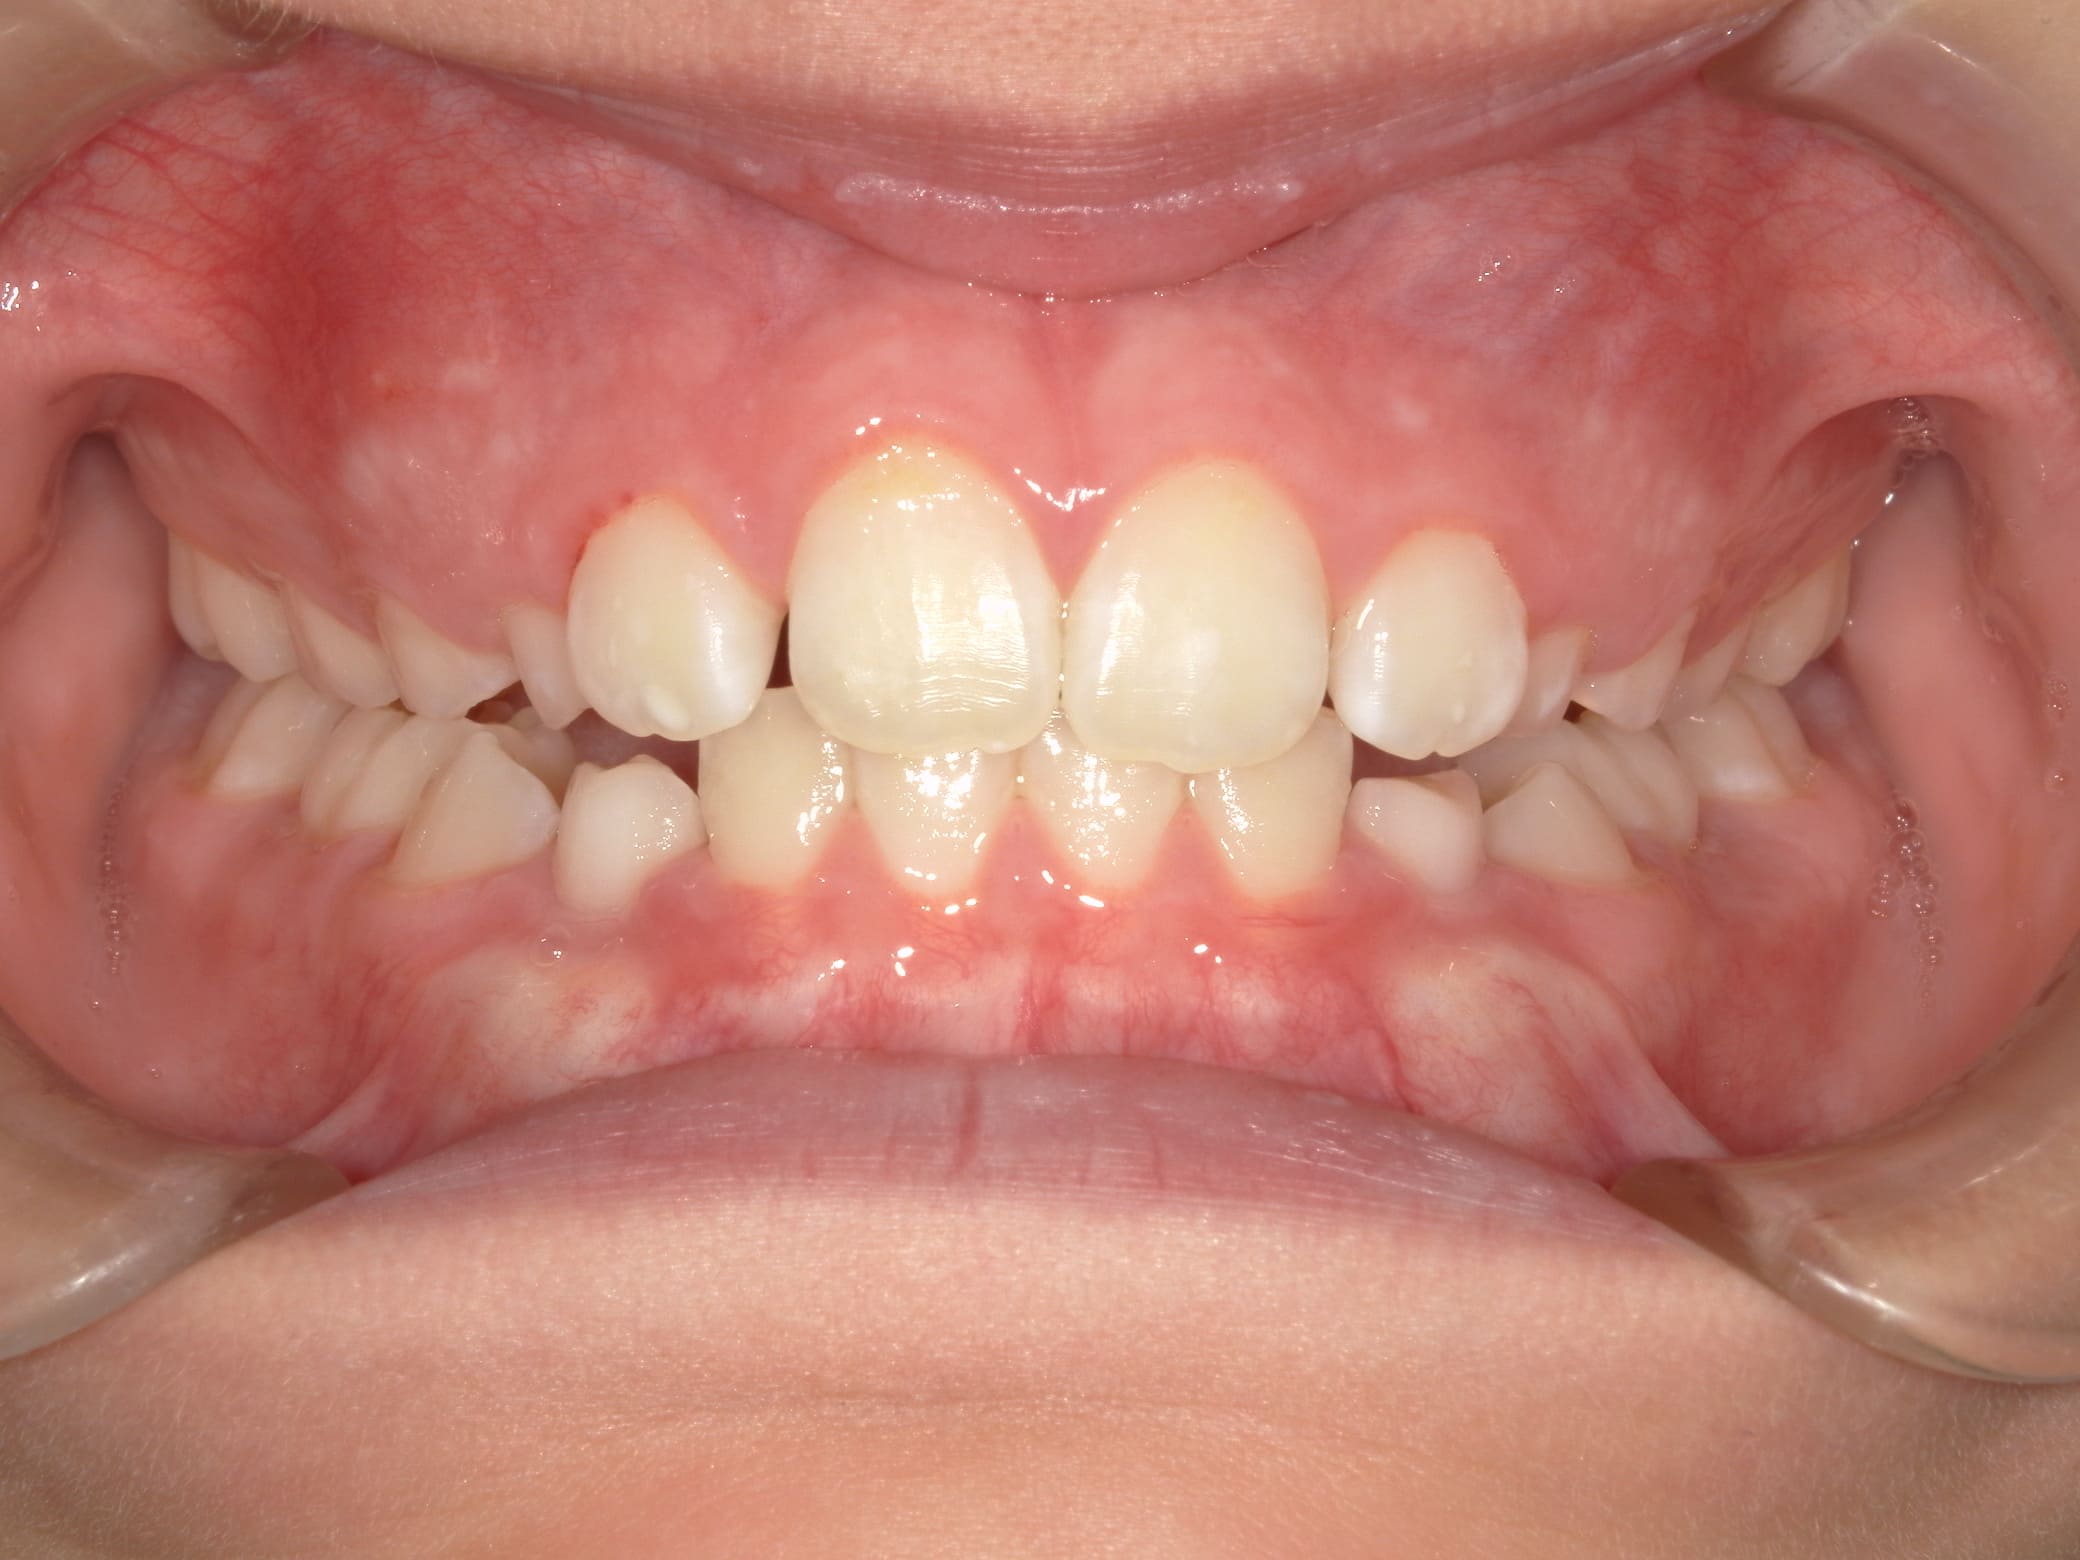

| 年齢・性別 | 8歳9ヶ月の女児 |

|---|---|

| 主訴 | 歯並びの乱れを気にされて来院された患者様です。将来的なスペース不足と歯のねじれ(翼状捻転)が懸念されました。 |

| 治療期間・回数 | 2年10ヶ月・19回 |

| 費用 | 430,000円(税別) |